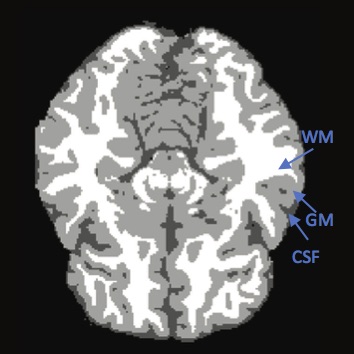

a) sample brain MRI image   b) segmented image

Brain MRI analysis is an essential task in many clinical applications. Fundamental components of structural brain MRI analysis include the classification of MRI data into specifict tissue types and the identification and description of specific anotomical structures. Among all the tissue types, the tissue elements we are typically interested in are: cerebrospinal fluid (CSF), gray matter (GM) and white matter (WM); see Figure b). The segmentation results are further used in different applications such as for analyzing anatomical structures, for studying pathological regions, for surgical planning, and for visualization purposes.